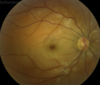

CRAO

1. Call ophtho 2. Intermittent digital massage with quick release 3. ASA 4. Inhalation of CO2/O2 or breath through paper bag 5. Topical beta blocker 6. Acetazolamide 7. Nitro 8. Hyperbaric osxygen 9. Consider intra-arterial lytcs